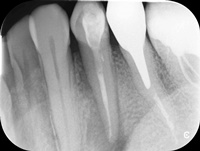

Trzykanałowa górna czwórka, nieczęsty przypadek.